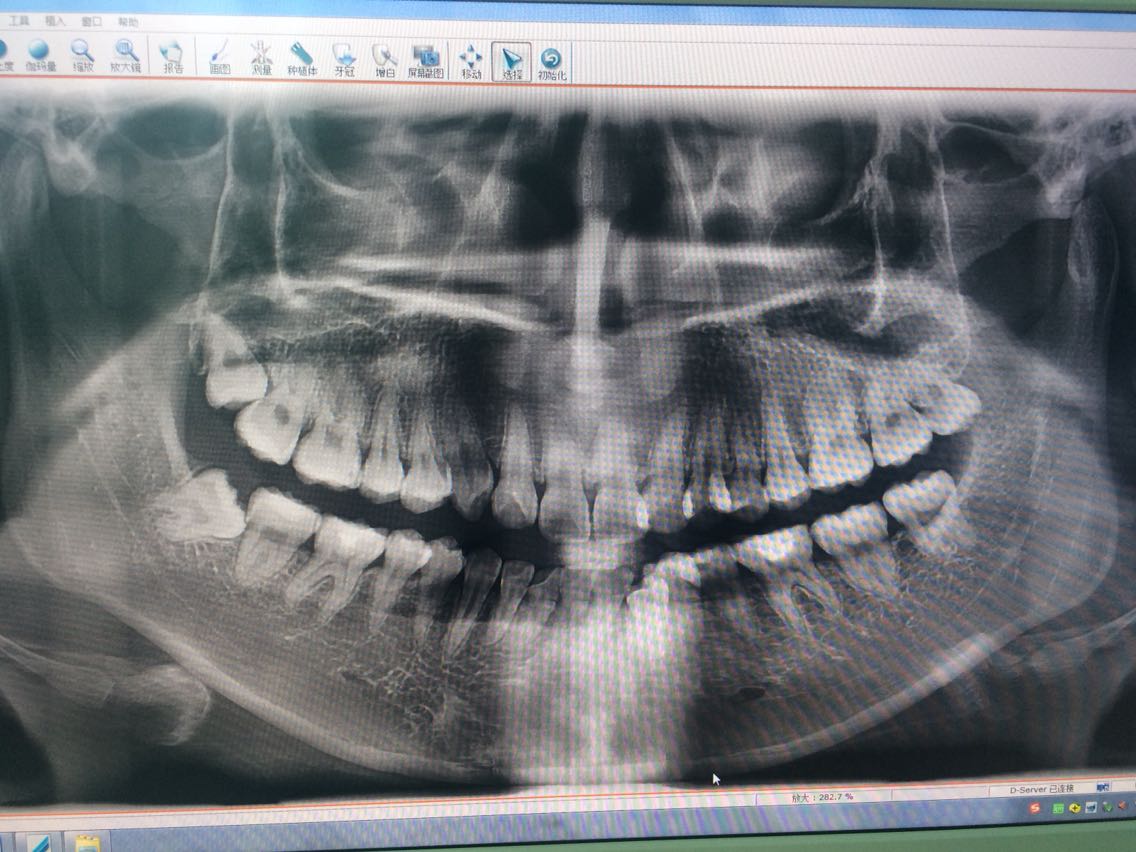

查体:颌面部左右对称,无畸形,无肿胀,余未见异常。 口内检查:口内未见C8萌出,触诊可触及C7远中磨牙后垫黏膜下坚硬体。C7无明显龋坏和牙体缺损,无松动,牙周无明显异常。A8远中牙冠少量萌出,近中部分位于A7牙冠远中下方,A7无明显龋坏和牙体缺损,无松动,牙周无明显异常。 曲面断层片:如图

诊断:A8低位前倾阻生,C8软组织埋伏前倾阻生。 治疗计划:拔除A8,C8 处理:告知患者病情,排除禁忌症,征得患者同意,签同意书,C8利多卡因阻滞麻醉,A8斯康杜尼浸润麻醉,C8切开,三角形切口,翻瓣,近中大部分位于A7牙冠下方,45度手机分牙,挺出远中半后,取出近中部分,清创,放置明胶碘仿于牙槽窝,缝合。A7一字型切开,翻瓣,分冠,清创,拔除放明胶碘仿于牙槽窝,缝合。无菌纱球压迫止血。给予消炎药口服。嘱注意事项,不适随诊。

随访:隔日随访,轻微疼痛,无明显不适。 讨论:此病例全程拔除只用了不到35分钟,可能对大多数医生来说并不存在什么困难。由于本人临床经验较少,认为复杂智齿,还是建议提前cbct检查,光靠曲面断层片,还是不大靠谱,就如本例C8显示未近中阻生,但翻瓣后发现,前倾角度并没有平片上显示那么大。所以,个人认为,合理的利用影像学检查,可以更好的做出术前分析,减少不必要的麻烦,缩短手术时间,跟病人带来更好的体验。不足之处,还请各位多多指出。谢谢!